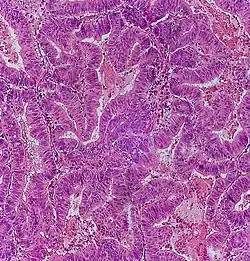

Adenocarcinoma is a malignant epithelial tumor, originating from superficial glandular epithelial cells lining the colon and rectum. It invades the wall, infiltrating the muscularis mucosae layer, the submucosa, and then the muscularis propria. Tumor cells describe irregular tubular structures, harboring pluristratification, multiple lumens, reduced stroma ("back to back" aspect). Sometimes, tumor cells are discohesive and secrete mucus, which invades the interstitium producing large pools of mucus. This occurs in mucinous adenocarcinoma, in which cells are poorly differentiated. If the mucus remains inside the tumor cell, it pushes the nucleus at the periphery, this occurs in "signet-ring cell." Depending on glandular architecture, cellular pleomorphism, and mucosecretion of the predominant pattern, adenocarcinoma may present three degrees of differentiation: well, moderately, and poorly differentiated.[5]

- Invasive adenocarcinoma commonly displays:[6]

- Varying degrees of gland formation with tall columnar cells

- Frequently desmoplasia

- Dirty necrosis, consisting of extensive central necrosis with granular eosinophilic karyorrhectic cell detritus.[6][7] It is located within the glandular lumina,[7] or often with a garland of cribriform glands in their vicinity.[6]